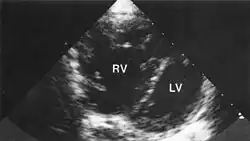

Гипертрофия правого желудочка очень заметна. Правый желудок намного больше левого, что явно указывает на заболевание лёгких.

Гипертрофия ПЖ явно указывает на лёгочное заболевание.